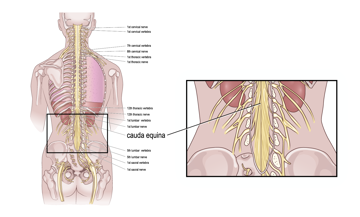

Erfahren Sie mehr darüber, was das Cauda-equina-Syndrom ist, welche Auswirkungen es auf Blase und Darm hat und wie man Blasen- und Darmsymptome bei Cauda equina behandelt.

Erfahren Sie mehr darüber, was das Cauda-equina-Syndrom ist, welche Auswirkungen es auf Blase und Darm hat und wie man Blasen- und Darmsymptome bei Cauda equina behandelt.